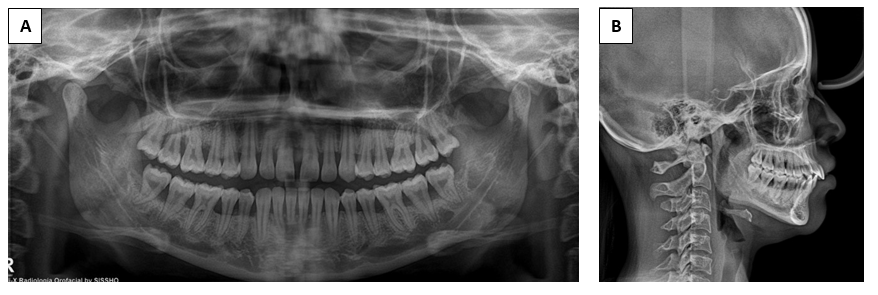

Orthodontic evaluation revealed a normofacial biotype with a skeletal Class II Division 1 relationship, no vertical discrepancies, dental protrusion, and presence of diastemas (Figures 4–5). The periodontium was stable at the onset of orthodontic therapy. Conventional fixed appliances (Roth prescription, 0.022” x 0.028”) were placed in December 2024. The archwire sequence consisted of NiTi 0.014”, NiTi 0.018”, NiTi 0.020” x 0.020”, and NiTi 0.019” x 0.025”. Space closure was achieved using elastic chains and 0.028” stainless steel ligatures. The orthodontic treatment plan was divided into three phases: (1) alignment and leveling, (2) space closure, and (3) finishing and detailing of occlusion. The patient did not present any functional alterations of the temporomandibular joint, with a stable centric relation confirmed using Whip-Mix® articulator mounting.

Figure 5 A) panoramic radiograph, B) lateral cephalometric radiograph (2024)